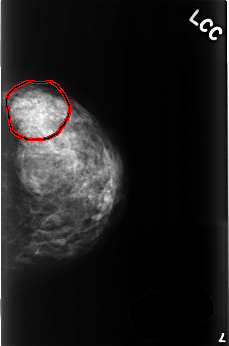

C_0509_1.LEFT_CC

LEFT_CC LINES 4496 PIXELS_PER_LINE 2968 BITS_PER_PIXEL 12 RESOLUTION 50 OVERLAY

FILE: C_0509_1.LEFT_CC.OVERLAY

TOTAL_ABNORMALITIES 1

ABNORMALITY 1

LESION_TYPE CALCIFICATION TYPE AMORPHOUS DISTRIBUTION SEGMENTAL

ASSESSMENT 4

SUBTLETY 1

PATHOLOGY BENIGN

TOTAL_OUTLINES 1

BOUNDARY